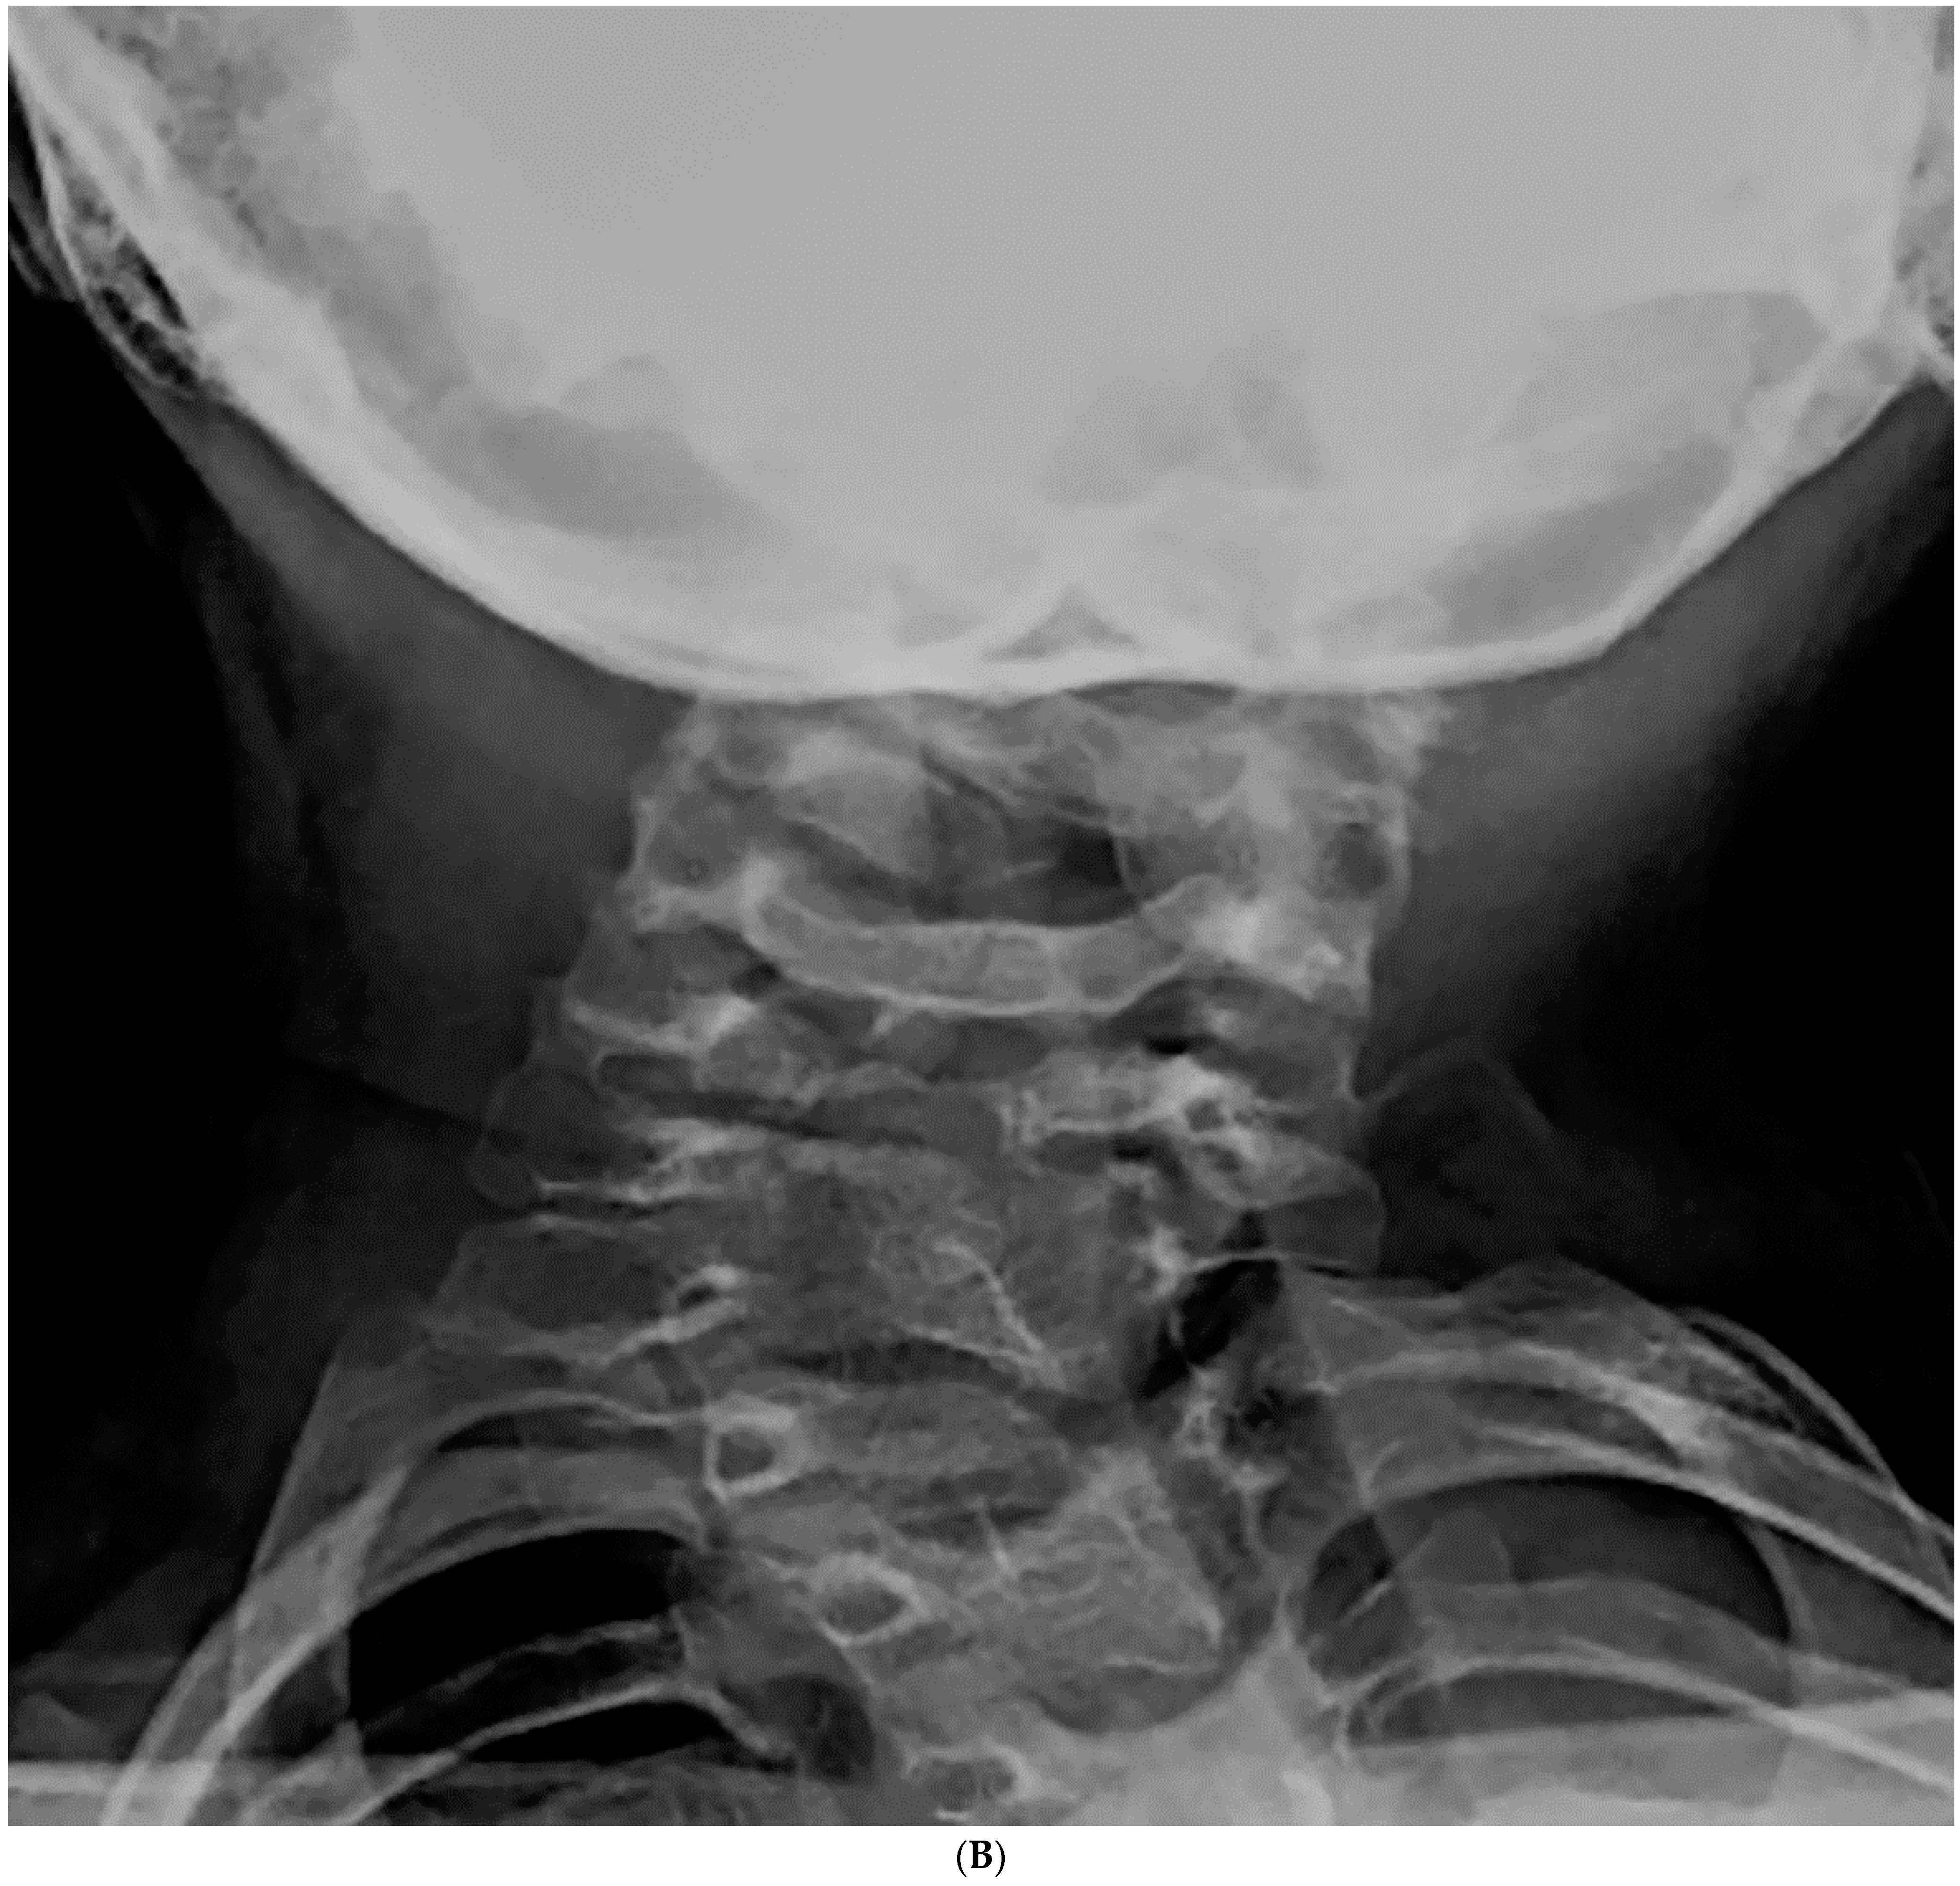

Figure 2.

(A–C). An 8-year-old boy diagnosed with CCS with progression of cervical deformity and compensatory curve. (A) PA radiograph shows a C7 hemivertebra. (B) Lateral radiograph. (C) Coronal CT highlights the left C7 hemivertebra. Patients with thoracic or lumbar vertebral anomalies (such as hemivertebrae, butterfly vertebrae, etc.) were excluded from this study. This was to best ensure that any compensation in the thoracic or lumbar regions was not due to vertebral anomalies in those regions.